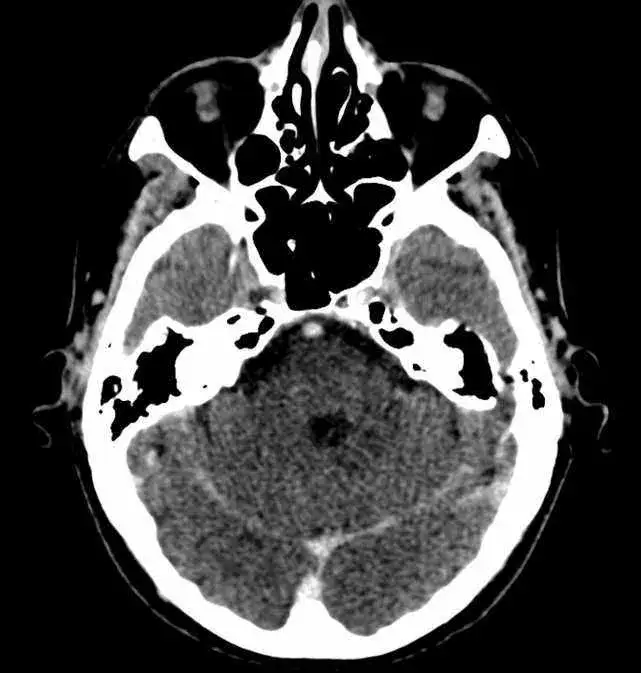

- Diagnostyka schorzeń zatoki klinowej obejmuje badania takie jak tomografia komputerowa i endoskopia.

Znajomość lokalizacji zatoki klinowej jest istotna nie tylko dla anatomii, ale również w kontekście diagnostyki i leczenia schorzeń zatok. Właściwe zrozumienie jej położenia ułatwia lekarzom przeprowadzanie zabiegów medycznych oraz diagnostycznych, takich jak endoskopia czy tomografia komputerowa. W kontekście medycznym zatoka klinowa jest często badana, ponieważ jej schorzenia mogą prowadzić do poważnych problemów zdrowotnych.

W przypadku problemów z zatoką klinową, istotne jest przeprowadzenie odpowiednich badań diagnostycznych, aby postawić właściwą diagnozę. Wśród najczęściej stosowanych metod znajduje się tomografia komputerowa (TK), która pozwala dokładnie ocenić stan zatok. TK jest szczególnie przydatna w identyfikacji ewentualnych zmian strukturalnych, takich jak polipy czy zapalenie zatok. Inną popularną metodą jest endoskopia, która umożliwia bezpośredni wgląd do wnętrza zatok oraz pobranie próbek do analizy.

Diagnostyka zatoki klinowej obejmuje różne badania, które pomagają w ocenie jej stanu. Tomografia komputerowa jest jednym z najskuteczniejszych narzędzi, które dostarcza szczegółowych obrazów zatok oraz okolicznych struktur. Endoskopia to kolejna metoda, która pozwala lekarzom na bezpośrednie zbadanie wnętrza zatoki klinowej, co może być szczególnie przydatne w przypadku podejrzenia infekcji. Dodatkowo, lekarze mogą zlecić badania laboratoryjne, takie jak analiza wydzieliny z nosa, aby ustalić, czy występują jakiekolwiek infekcje bakteryjne lub wirusowe.

| Badanie | Cel | Oczekiwane wyniki |

|---|---|---|

| Tomografia komputerowa | Ocena struktury zatok | Wykrycie zmian, np. zapalenie, polipy |

| Endoskopia | Bezpośredni wgląd do zatok | Pobranie próbek, ocena stanu zapalnego |

| Badania laboratoryjne | Analiza wydzieliny z nosa | Ustalenie obecności infekcji |